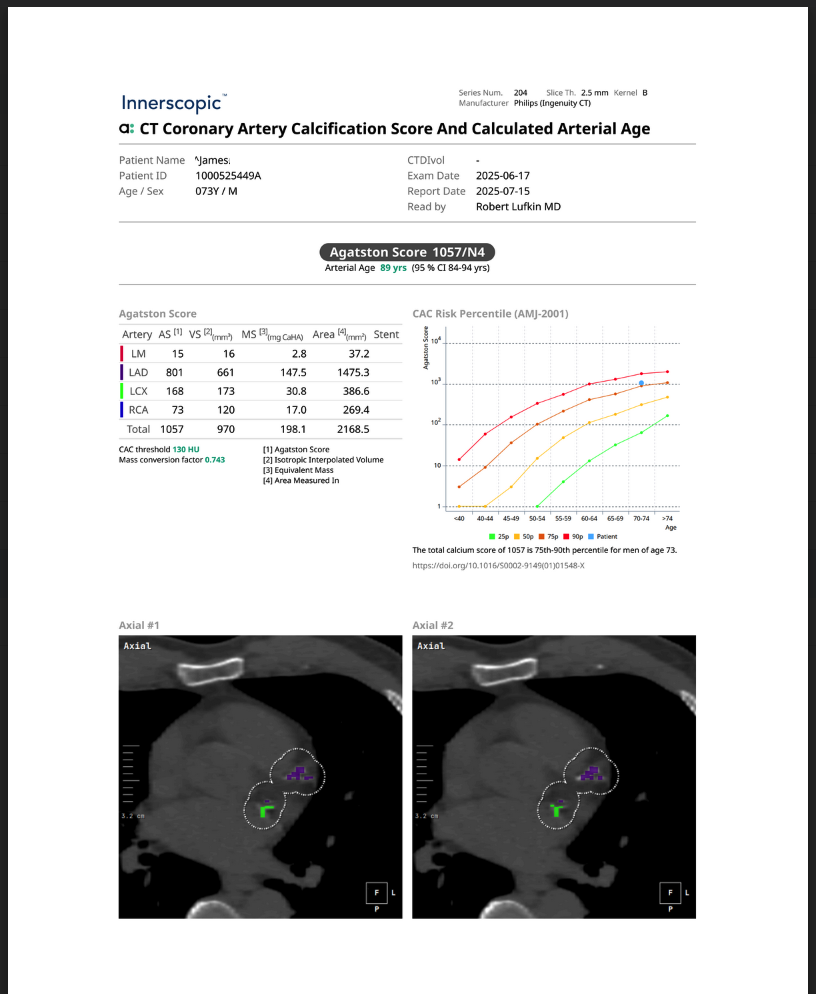

Traditional risk assessments for heart disease rely on blood tests, genetics, and family history, but these only estimate probability—not actual disease. CT Coronary Artery Calcium (CAC) Scoring allows you to see the disease itself by measuring calcified plaque buildup in the coronary arteries. This non-invasive scan provides a direct visualization of early atherosclerosis, helping to identify individuals at risk for heart attacks and cardiovascular events—even if their cholesterol and other markers appear normal. By knowing your CAC score, you and your doctor can create a targeted prevention plan to slow or reverse plaque progression and optimize heart health before symptoms develop. In fact, the CT Coronary Artery Calcium Score has been recently shown to be one of the best predictors of a heart attack.

CT CALCULATED ARTERIAL AGE

Cardiovascular disease risk isn’t just about cholesterol levels or family history—it’s about the actual condition of your arteries. CT Calculated Arterial Age translates coronary artery calcium (CAC) score into an easily understandable metric: the biological age of your arteries. Since calcium buildup in the arteries can develop at different rates based on factors like age, sex, and genetics, this test provides a more personalized assessment of vascular health. By comparing arterial age to chronological age, individuals can better understand their true cardiovascular risk and take proactive steps to slow or even reverse vascular aging through lifestyle and medical interventions.